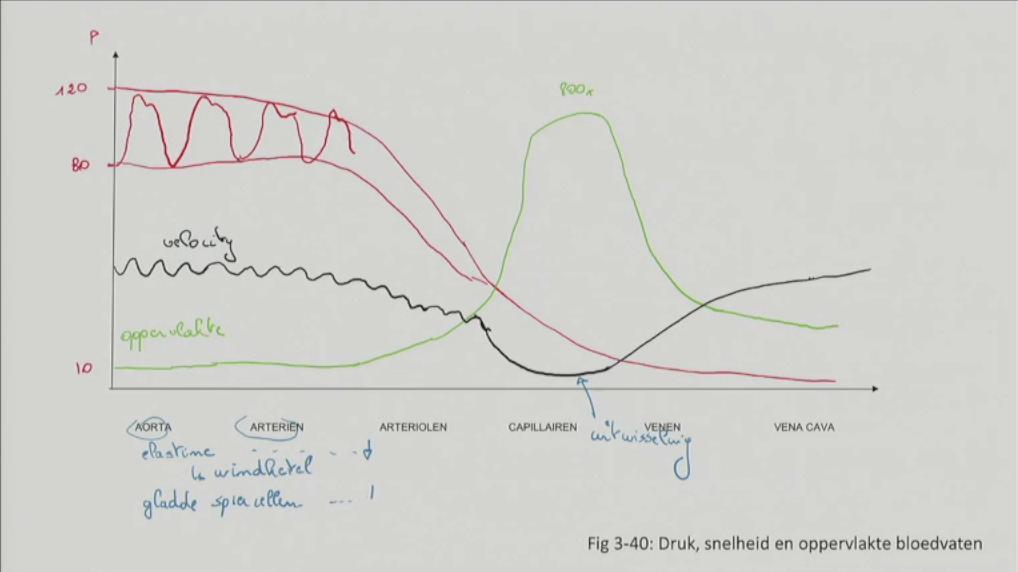

Fig 3.40: Druk, snelheid en oppervlakte bloedvaten

elastine (vooral in aorta en grote arterien) windketel effect uitwisseling t.h.v. capillairen gladde spierencellen (neemt af van aorta tot vv. cavae)